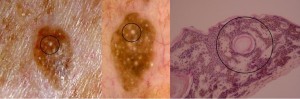

Invaginations of the epidermis filled with keratin called pseudohorn cysts (comedo-like cysts on dermoscopy) on dermoscopy)are characteristic of these lesions. The term “horn cysts” (milia-like cysts on dermoscopy), contrarily to pseudohorn cyts do not communicate with the surface. Let us underline that cysts tend to be over estimated and pseudohorn cysts underestimated due to the histological sections which are two dimensional.

The acanthotic {Kirkham, 1997}sometimes pigmented epidermis consists of columns of basaloid cells with pseudohorn cysts and horn cysts in between {Wade, 1979}.

B. Reticulate (or adenoidal)

The epidermis is characterised by a thin strand of basaloid cells which extend from the follicular keratinocytes and intermingle with each other {Wade, 1979}. This type often displays focal areas of hyperkeratosis, areas where pseudocysts and horn cysts are to be found{Kirkham, 1997}.